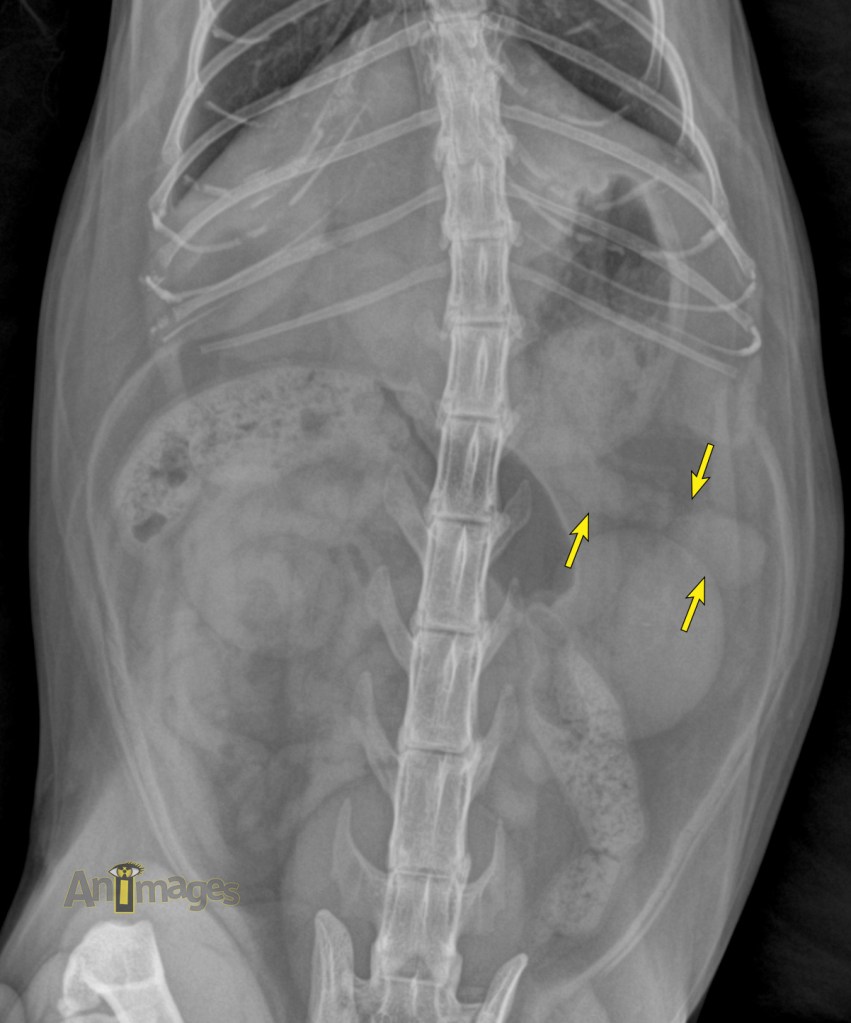

ventrodorsale